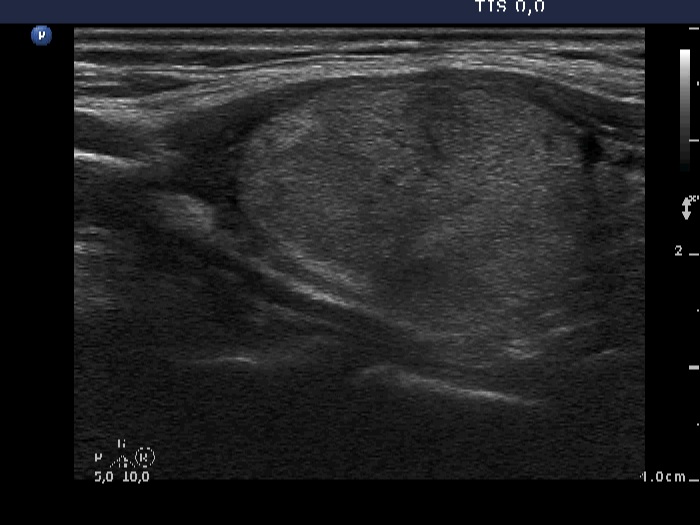

Ethanol sclerotherapy: non-toxic solid nodules - Case 5

Twelve years after the therapy (ultrasonographic picture 7)

Middle part of the left lobe, longitudinal scan.